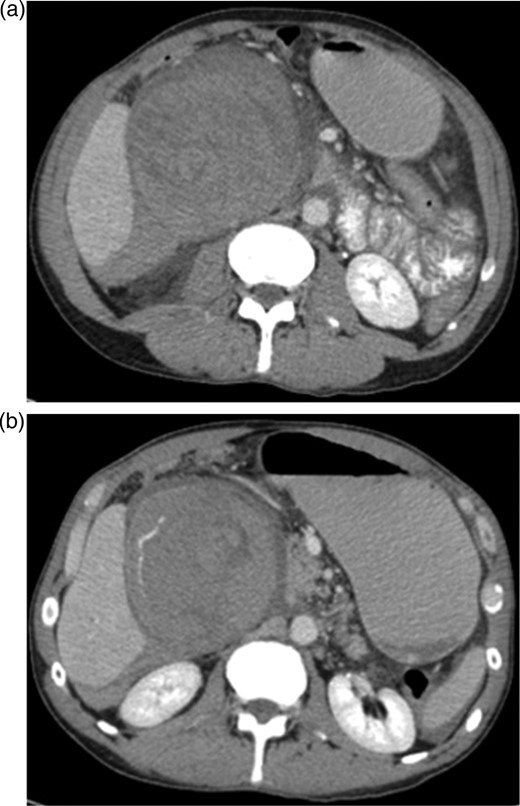

An ultrasound was done showing a mass in the right upper quadrant with no visualization of the gallbladder and no evidence of biliary tree dilatation. Therefore, a CT scan was performed which showed a large haematoma in the gallbladder fossa, which distends the gallbladder wall causing mass effect (Fig. 1a and b). Furthermore, active extravasation of IV contrast was seen. Initially, this was not clear if the haematoma is arising from the liver or within the gallbladder. Given his haemodynamic stability he was taken to the interventional angiography suite for an arteriogram of his abdominal aorta and splanchnic vessels. The bleeding was localized to a branch of the cystic artery and no pseudoaneurysm was identified (Fig. 2). Then, embolization of cystic artery with gelfoam material was performed. Since, embolization of the cystic artery proper was done, the decision was made to explore the patient and perform a cholecystectomy. Prior to the operation the patient became tachycardic at 100 with a systolic blood pressure of 90 and a diastolic of 60. His repeat haemoglobin was 10.1. Appropriate resuscitation with blood transfusion was performed.

(a and b) CT scan upper abdomen showing a large haematoma in the gallbladder fossa, which distends the gallbladder wall causing mass effect.